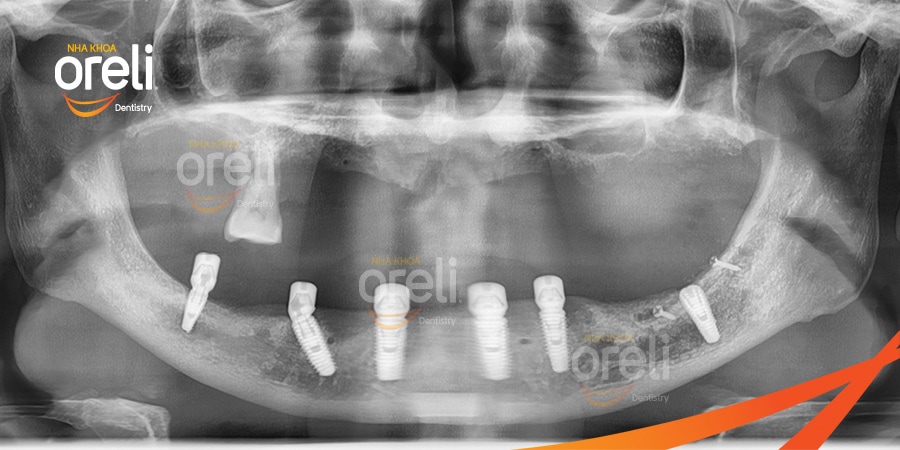

Ca cấy ghép răng Implant toàn hàm dưới tại Oreli

Ca cấy ghép răng Implant toàn hàm trên và dưới tại Oreli

Cấy ghép Implant toàn hai hàm

Ca cấy ghép Implant toàn hàm dưới có dời ống thần kinh răng dưới tại Oreli